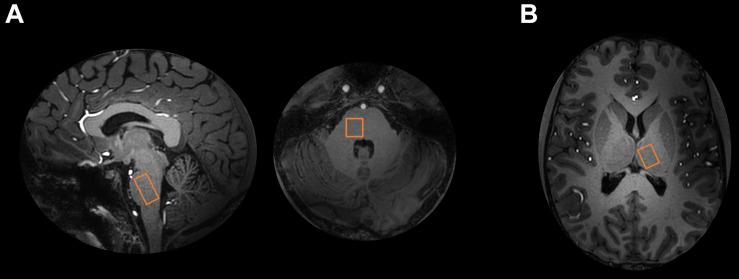

Glutamate detection in pons and thalamus using proton magnetic resonance spectroscopy (H-MRS) after an intervention is of interest for studying various brain disorders. However, H-MRS in these brain regions is challenging and time-consuming, especially in longitudinal study designs. H-MRS of more cortical structures at the ultrahigh magnetic field strength of 7T yields an improved spectral output, including separation of the glutamate signal from the glutamine signal, in a shorter and more feasible scan time, as compared to conventional clinical field strengths. For this purpose, we compared the feasibility of H-MRS at 3T and 7T in pons and thalamus by applying a longitudinal study design of repeated measures on same day and three separate days at both field strength in five healthy participants. Total H-MRS acquisition time was reduced by a factor 3.75 for pons and by a factor 3 for thalamus at 7T as compared to 3T. We found higher spectral signal-to-noise ratio (SNR) ( < 0.001), lower linewidth ( = 0.001) and lower Cramér-Rao lower bounds (CRLB) ( < 0.001) for the combined glutamate and glutamine signal (Glx) in thalamus at 7T as compared to 3T. In pons, CRLB of Glx and SNR were lower at 7T ( = 0.002 and = 0.006), with no differences in linewidth compared to 3T. Mean within-subject variability of Glx concentration estimates was lower at 7T compared to 3T for both pons and thalamus. At 7T, it was possible to assess glutamate and γ-aminobutyric acid (GABA) simultaneously in pons and thalamus. In conclusion, H-MRS at 7T resulted in improved spectral quality while allowing shorter scan times than at 3T as well as estimation of the pure glutamate signal in pons and thalamus. This opens up the opportunity for multimodal study designs and multiregional subcortical H-MRS research. Glutamate and GABA measurement at 7T in pons and thalamus is advantageous for future investigations of excitatory-inhibitory mechanisms in brain disorders.

干预后使用质子磁共振波谱(H-MRS)检测脑桥和丘脑的谷氨酸,对于研究各种脑部疾病具有重要意义。然而,在这些脑区进行H-MRS具有挑战性且耗时,尤其是在纵向研究设计中。与传统临床场强相比,在7T超高磁场强度下对更多皮质结构进行H-MRS,可在更短且更可行的扫描时间内获得改进的光谱输出,包括将谷氨酸信号与谷氨酰胺信号分离。为此,我们通过对五名健康参与者在3T和7T场强下同一天和三个不同日期进行重复测量的纵向研究设计,比较了脑桥和丘脑在3T和7T时H-MRS的可行性。与3T相比,7T时脑桥的总H-MRS采集时间减少了3.75倍,丘脑减少了3倍。我们发现,与3T相比,7T时丘脑谷氨酸和谷氨酰胺联合信号(Glx)的光谱信噪比(SNR)更高(<0.001)、线宽更低(=0.001)以及克莱姆-拉奥下界(CRLB)更低(<0.001)。在脑桥中,7T时Glx的CRLB和SNR更低(=0.002和=0.006),与3T相比线宽无差异。脑桥和丘脑的Glx浓度估计的平均受试者内变异性在7T时比3T更低。在7T时,可以同时评估脑桥和丘脑中的谷氨酸和γ-氨基丁酸(GABA)。总之,7T时的H-MRS提高了光谱质量,同时允许比3T更短的扫描时间,并能估计脑桥和丘脑中的纯谷氨酸信号。这为多模态研究设计和多区域皮质下H-MRS研究提供了机会。在7T时测量脑桥和丘脑中的谷氨酸和GABA,有利于未来对脑部疾病中兴奋-抑制机制的研究。